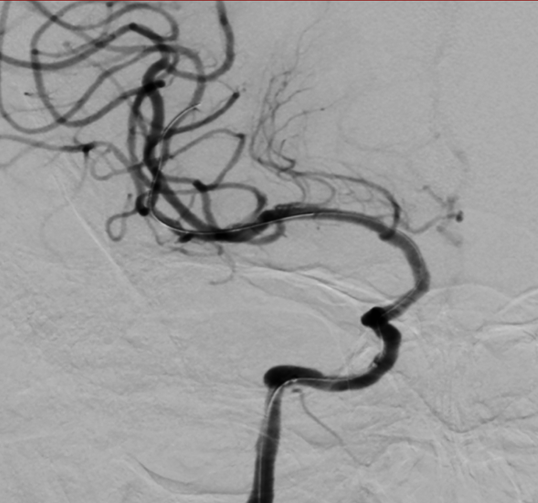

术后影像及检查

术后造影。

手术总结

术中微导丝远端放置在大脑中动脉M1段,小心通过狭窄,避免栓子脱落及夹层出现。赛诺神畅 NOVA DES®内药物洗脱支架可视性及成型完美,期待能降低支架内再狭窄的发生。

手术技巧

通路的建立,尤其重要,中间导管接近病变处,方便球囊及支架顺利通过狭窄段,小球囊预扩方便支架通过,预扩后将中间导管通过狭窄段,将支架准确放置在狭窄段,撤回中间导管,缓慢释放支架,避免出现夹层及斑块脱落,选择合适的支架,避免后扩。